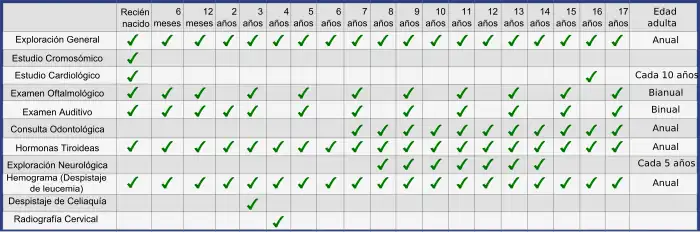

En 1981 se diseñó el primer Programa de Salud específico para personas con SD, pero el más ampliamente aceptado y difundido en la comunidad científica es el diseñado por el Down Syndrome Medical Interest group (DSMIG).[51] En estos programas de salud se contemplan las actuaciones preventivas mínimas para un adecuado diagnóstico precoz y seguimiento de las enfermedades o complicaciones que se pueden presentar, mejorando significativamente el pronóstico de estas personas. Por otra parte los programas, cada vez más extendidos, de estimulación precoz, y el cambio progresivo de mentalidad que la sociedad está experimentando con respecto a la discapacidad intelectual son los principales motivos de la gran transformación que se está viviendo en torno a las personas con SD. Hace apenas unas décadas estas personas eran apartadas de la sociedad en instituciones, o escondidas por sus progenitores, basándose en un falso complejo de culpa. A pesar del enorme esfuerzo que aún queda pendiente se ha comprobado cómo un entorno basado en la aceptación, en la adaptación de los métodos de aprendizaje y en la virtud de la diversidad está dotando a las personas con SD de la autonomía suficiente como para trabajar, vivir en pareja o desarrollar habilidades artísticas impensables hace muy poco tiempo.[52]